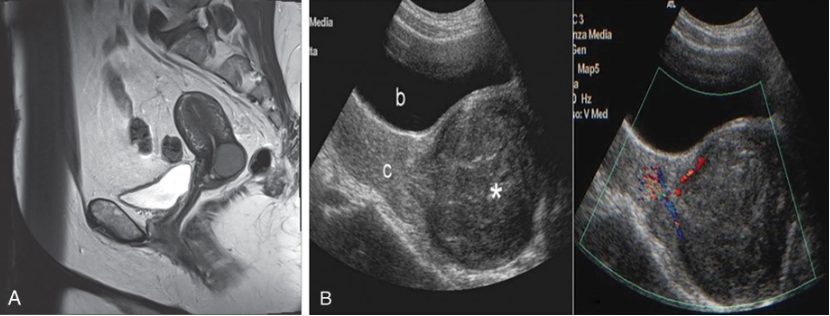

Benign disease

Diffuse or focal

Global infiltration of endometrium

Sonographically presents as bulky enlarged uterus without focal mass

Adenomyosis is ectopic occurrence of endometrial tissue within myometrium; more common in

posterior aspect

The tissue penetration usually reaches a depth of at least 2.5 mm from the basal layer of the

endometrium.

Adenomyosis may arise from multiple pregnancies and deliveries with subsequent uterine shrinking.

Elevated estrogen levels may also promote the growth of myometrial islands of endometrial tissue.

Adenomyosis is often classified into diffuse and focal forms. The more common form is diffuse

adenomyosis.

It represents a reactive hypertrophy of the myometrial muscle, which produces uterine enlargement

but usually not to the extent seen with leiomyomas.

Focal adenomyosis is sometimes called adenomyoma, referring to isolated implants that typically

cause reactive hypertrophy of the surrounding myometrium and produce diffuse uterine enlargement.

Less common than the diffuse form, focal adenomyosis (adenomyoma) lacks a hypoechoic border that

is seen with fibroids, not endometriosis. Adenomyosis can be appropriately managed with hormone

therapy.

Patients with adenomyosis are often multiparous and older than patients with endometriosis.

The patient presents with heavy, painful abnormal menses, and on physical examination, the uterus is

Sonographically, diagnosis may be difficult.

Most common presentation of extensive adenomyosis is:

➢ Diffuse uterine enlargement

➢ Thickening of posterior myometrium

➢ Indistinct border between endometrium and myometrium (involved area being slightly more

anechoic than normal myometrium)

Has been described as Swiss cheese or honeycomb pattern

Calcifications resulting from prior instrumentation are seen along inner myometrium and cervix.

Doppler studies have also proven helpful in differentiating uterine pathology, as color flow studies of

uterine masses show that myomas and sarcomas typically demonstrate a feeding artery, but

adenomyosis rarely demonstrates feeding arteries.

Adenomyosis is not always reliably diagnosed by ultrasonography, and

caution is advised because these findings are similar in appearance to

uterine myomas, muscular hypertrophy, myometrial contractions,

endometritis, endometrial carcinoma, and the presence of increased

endometrial secretions.

The presence of myomas has been shown to limit the ability to diagnose

the severity of adenomyosis.

Although not reliably diagnosed by ultrasonography, adenomyosis is well

characterized by MRI, which currently is thought by many to be the

best technique for the presurgical diagnosis of adenomyosis.

Adenomyosis